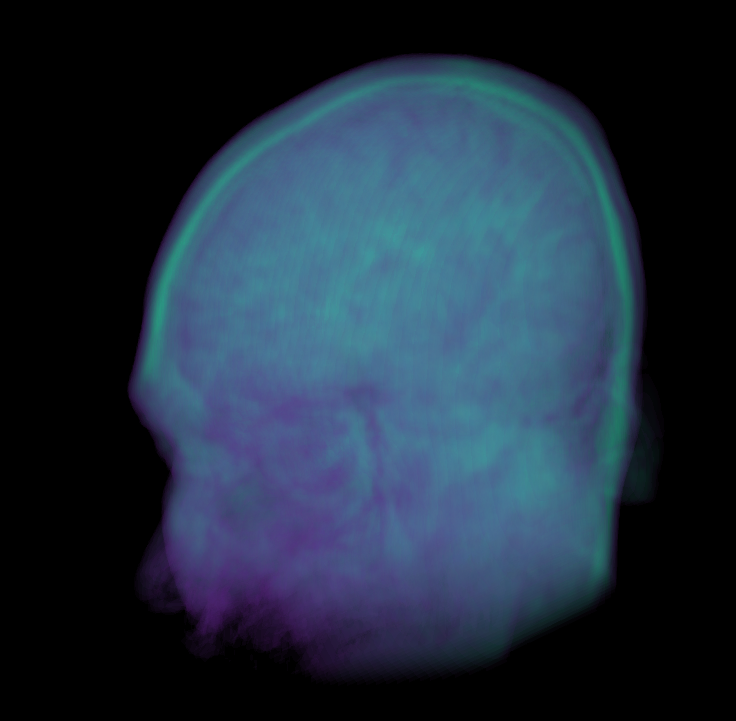

Image Volumes

2D

3D

Marching Cubes creates 3D Meshes

Bill Lorensen 1987